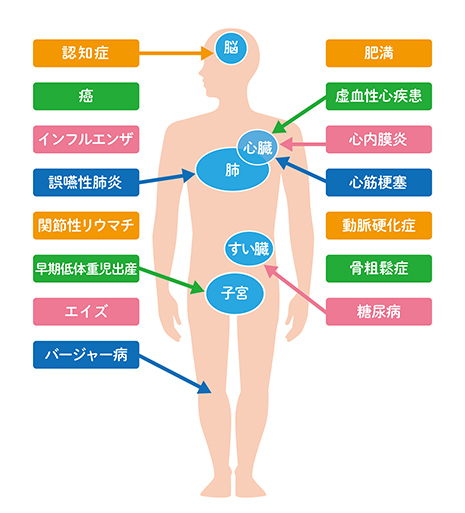

歯周病は全身疾患と深い関係にあり、歯周病菌が体内に入り込むと、全身の健康にも影響を及ぼす恐ろしい病気です。例えば糖尿病や誤嚥性肺炎、心筋梗塞などのほかにも妊娠中に歯周病になると早産及び低体重児出産となる可能性もあります。

全身の健康のためにも歯周病の予防や軽症のうちに治療に取り組みましょう。